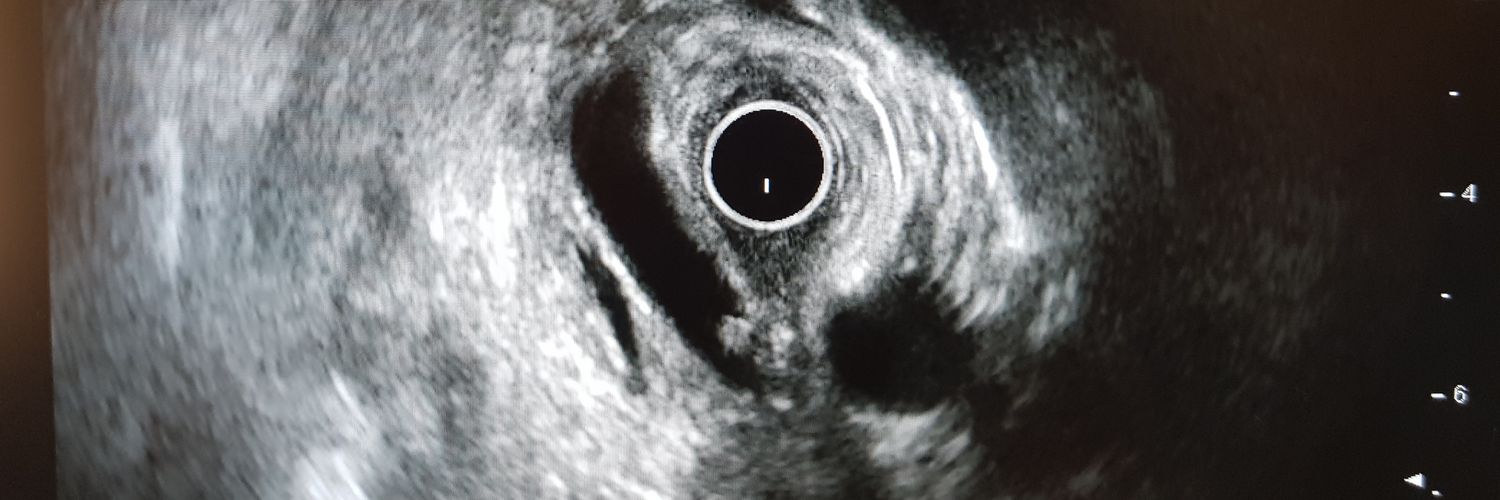

“Common bile duct stone on EUS”:

Basic EUS images

youtu.be/ow0fHYMpdXg